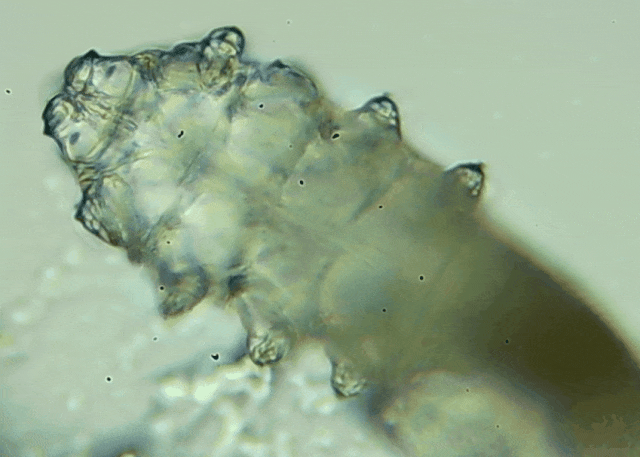

蠕形螨是一類肉眼看不見(jiàn)的寄生螨,常見(jiàn)的有毛囊蠕形螨和皮脂蠕形螨,常駐在人類的毛囊和皮脂腺里,尤其是眼睛的瞼板腺和睫毛根部。數(shù)量少時(shí),蠕形螨能與人體“和平共處”,但一旦你免疫力下降、油脂分泌旺盛或清潔不到位,他們就會(huì)以你難以想象的速度瘋狂繁殖。